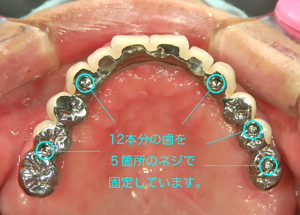

多数インプラントの構成

コラム「多数インプラントの構成」の画像